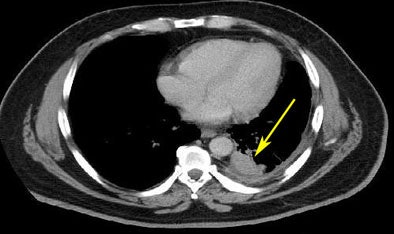

![]() |

| From the RIDER database, a lung cancer case is shown pretreatment (top) and post-treatment (bottom). |